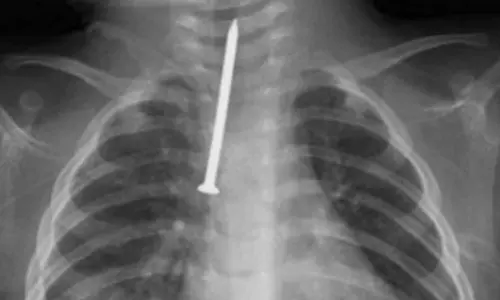

ശ്വാസനാളത്തിൽ കുടുങ്ങിയ ആണി പുറത്തെടുത്തു; റിയാദിൽ എട്ട് മാസം പ്രായമുള്ള കുഞ്ഞിന് പുതുജീവൻ